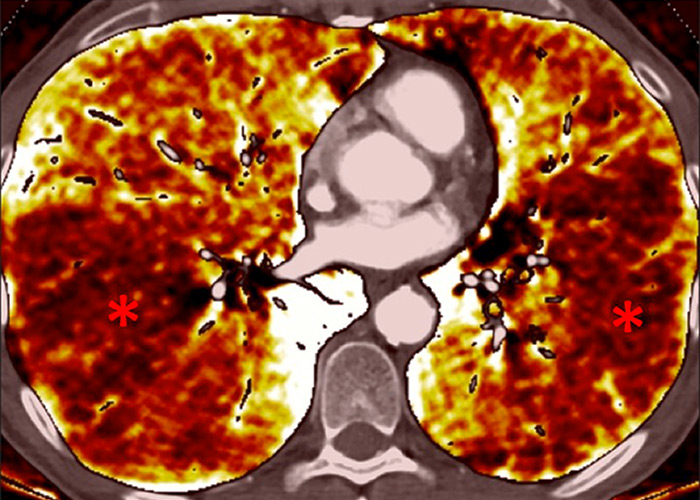

Figure 6

Perfusion heterogeneities in idiopathic pulmonary artery hypertension (stars) in two different patients (A/B). The dilatation of the arteries in pulmonary hypertension (arrows) is not always observed depending on the severity of pulmonary hypertension.

Nowadays, DECT imaging can be used for pathologies other than CTEPH and seems to offer advantages for PH characterisation because different DECT findings have been described in acute pulmonary embolism, CTEPH and idiopathic PAH (IPAH). In fact, perfusion defects are smaller and less defined in PAH than in CTEPH. This is likely due to focal under- and overperfusion as a result of the structural pulmonary vascular changes that occur in PH, which include vascular endothelial damage, cellular proliferation and occlusion in the distal pulmonary vasculature. Perfusion heterogeneities in DECT imaging are also common and seen in most cases of PAH. Findings of perfusion inhomogeneities related PAH have long been recognised in scintigraphy, and often are referred to as having a “mottled” pattern [42]. These perfusion defects are different from those seen in CTEPH, with nonsegmental and poorly defined defects (fig. 5). This heterogeneity is related to the severity of the disease. In PAH, this perfusion variability on scintigraphy is well correlated with pulmonary vascular resistance, as Talwar et al. showed [43]. Recently, similar results were published for DECT techniques (fig. 6). Ameli-Renani et al. described an increased enhancement of pulmonary arteries with reduced iodine lung perfusion in PH, and a good correlation of DECT perfusion heterogeneities with pulmonary vascular resistance; they showed a greater heterogeneity in parenchymal iodine maps in PH without pulmonary embolism [13]. The authors concluded that perfusion heterogeneities seen in DECT appear to be a direct reflection of pulmonary vascular resistance.